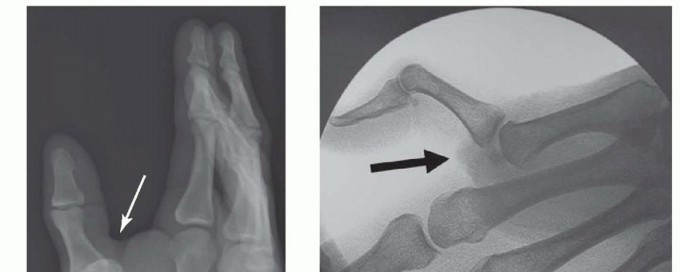

FIG 2 • X-rays showing MP joint dislocation on AP (A) and lateral (B) films. (continued)